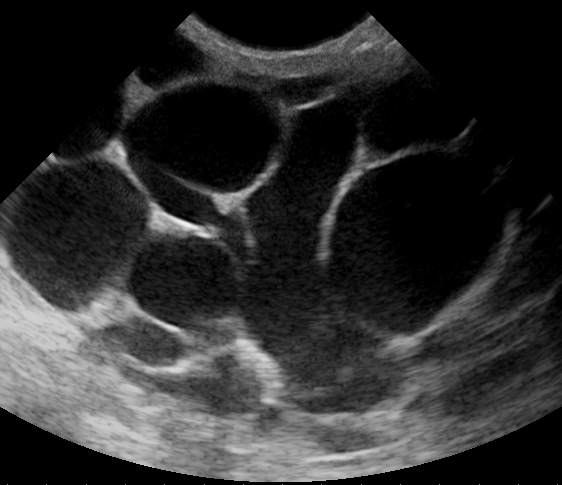

Fibrocystic Changes

Fibrocystic changes are the development of fibrosis and cysts in the breast.

The most common change in the premenopausal breast is fibrocystic change, which is assumed to be hormone mediated.

Fibrocystic change may manifest as a vague irregular lump.

Both breasts are affected by benign changes, however some fibrocystic-related changes are linked to an elevated risk for invasive cancer.

No increased risks are shown by fibrosis, cysts, or apocrine metaplasia.

Sclerosing adenosis and ductal hyperplasia both indicate greater risk of progression to malignancy.